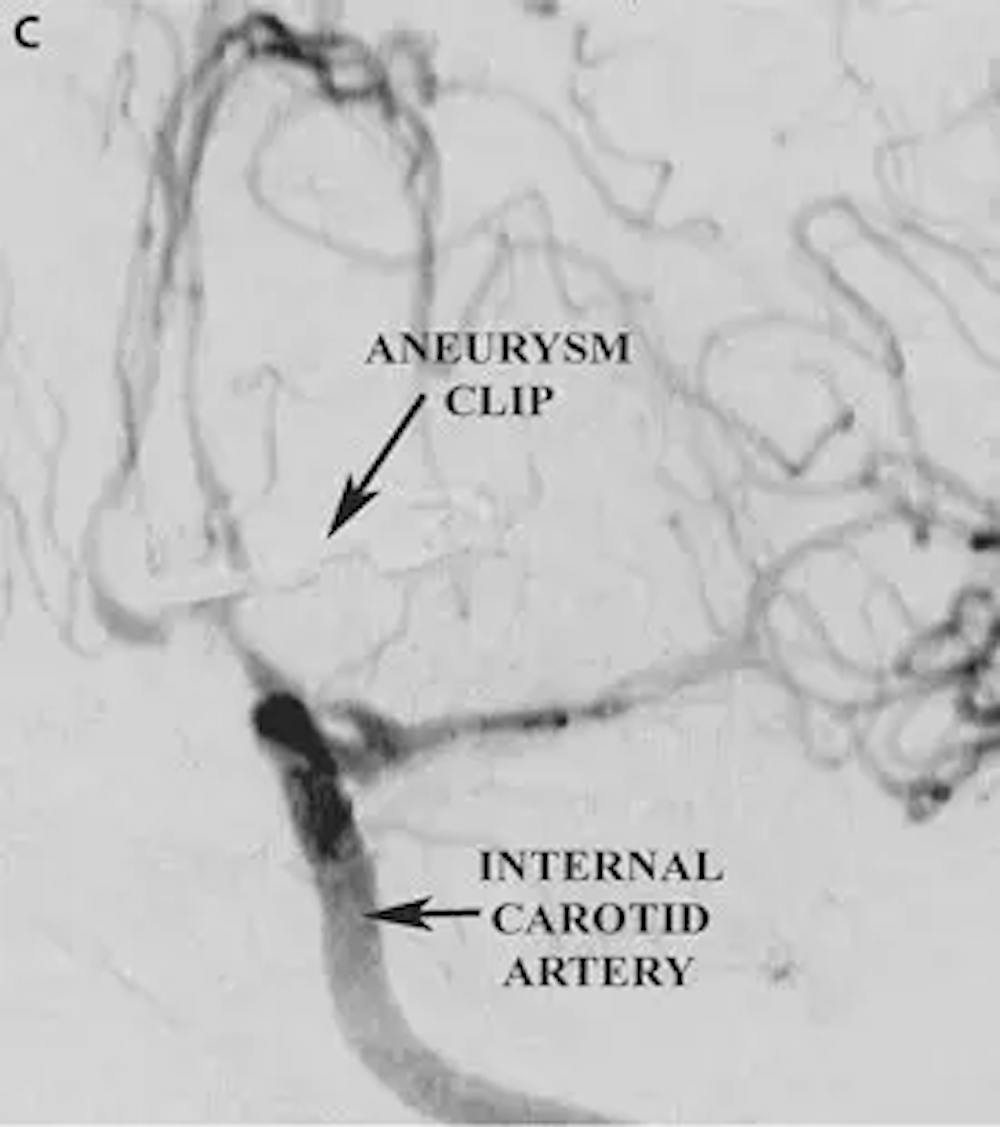

C) 수술 후 AP 혈관 조영술에서 전방 소통 동맥 동맥류의 클리핑을 보여주는 사진